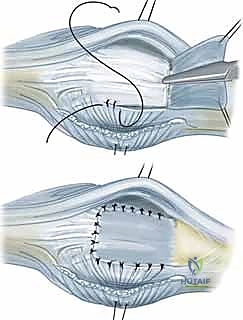

استئصال الغشاء الزليلي وتوسيط الوتر الباسط لمفصل MCP هو إجراء جراحي يعالج انحراف الأصابع وتشوهها الناتج عن التهاب المفاصل، خاصة الروماتويدي. يهدف إلى تخفيف الألم، استعادة ميكانيكا المفصل، وتحسين وظيفة اليد من خلال إزالة الأنسجة الملتهبة وإعادة محاذاة الأوتار.

الخلاصة الطبية السريعة: يُعد إجراء "استئصال الغشاء الزليلي وتوسيط الوتر الباسط لمفصل MCP" بمثابة طوق النجاة الجراحي الفعال لعلاج انحراف الأصابع وتشوهاتها المعقدة الناتجة عن التهاب المفاصل، وعلى رأسها التهاب المفاصل الروماتويدي. يهدف هذا التدخل الجراحي الدقيق إلى القضاء على الألم المزمن، واستعادة الميكانيكا الحيوية للمفصل، وتحسين الوظيفة الحركية لليد بشكل جذري. يتم ذلك من خلال الإزالة الدقيقة للأنسجة الزليلية الملتهبة (التي تدمر الغضاريف) وإعادة محاذاة الأوتار الباسطة المنزلقة إلى مسارها التشريحي الصحيح. تحت إشراف جراح خبير، تعود لليد قدرتها على أداء المهام اليومية بكفاءة ومظهر طبيعي.

في مركزنا، وتحت إشراف الأستاذ الدكتور محمد هطيف، ندرك تماماً حجم المعاناة الجسدية والنفسية، والتحديات الوظيفية الهائلة التي يواجهها مرضانا بسبب هذه الحالة المتقدمة. لذلك، نقدم حلاً جراحيًا متطوراً ومتخصصاً يُعرف باسم استئصال الغشاء الزليلي وتوسيط الوتر الباسط لمفصل MCP. هذا الإجراء الميكروسكوبي الدقيق مصمم بعناية فائقة لاستعادة ميكانيكا المفصل الطبيعية، إيقاف التدمير الغضروفي، تخفيف الألم بشكل نهائي، وتحسين وظيفة اليد ومظهرها بشكل ملحوظ للمرضى الذين يتم تقييمهم واختيارهم بعناية.

- وتر الباسطة الرقمية المشتركة (Extensor Digitorum Communis - EDC): هو اللاعب المركزي والنجم في إجراء اليوم الجراحي. يتم الاحتفاظ بهذا الوتر في المنتصف تماماً فوق قمة مفصل MCP بواسطة هياكل تُعرف بـ الأربطة السهمية (Sagittal Bands).

- تمزق الرباط السهمي الكعبري (Radial Sagittal Band Attenuation): التورم المستمر يضغط على الأربطة السهمية التي تثبت الوتر الباسط. نظراً لأن الرباط الكعبري أضعف بطبيعته، فإنه يتمدد أو يتمزق أولاً.

- الانزلاق الزندي للوتر الباسط (Ulnar Subluxation of EDC): بمجرد ضعف الرباط السهمي الكعبري، ينزلق وتر الباسطة (EDC) من أعلى قمة المفصل نحو الوادي الزندي بين الأمشاط. عندما يحدث هذا، يفقد الوتر قدرته على بسط الإصبع بفعالية، وبدلاً من ذلك، تصبح قوة سحبه مساهمة في زيادة الانحراف الزندي للأصابع.